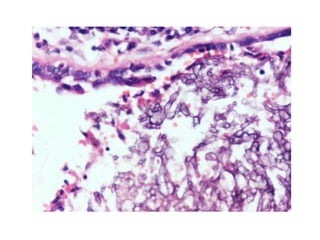

• #41 40 x of pnemocystis h e the organisms spread to the interstitium of the lung, widen alveolar walls, and invade blood vessel walls (arrow). Some authors believe that alveolar walls then undergo lysis to form cavities [3]. Other authors have attributed the lysis to ischemic necrosis caused by a necrotizing angiitis [4]. Note that there is little inflammatory reaction.

• #42 An adjacent section was stained with the GMS stain to show the presence of spore cases both in the alveolar space (A) and alveolar wall (W).

• #43 The foamy pink exudate stains with the PAS stain after diastase digestion. It is composed of trophic forms, surfactant phospholipids, cell debris, and host-derived proteins [2]. The faint dots in the exudate correspond to nuclei of the trophic forms.

CASE 5 • 29year old female • C/o cough , worsening since weeks, low grade fever • H/0 smoking half pack a day • K/C/O- RVD • O/E- Normal • Anticubital veins- Needle Track • Lungs- Decreased breath sounds, ronchi • Chest Xray- Ground glass appearance